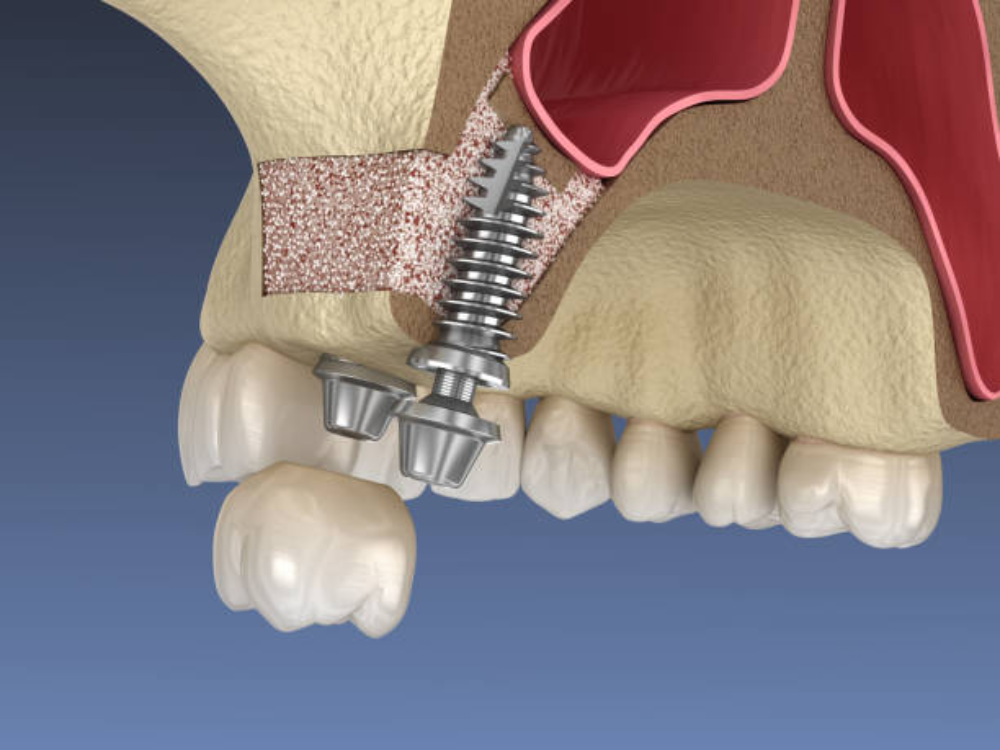

Sinus Lift – [Price TBD]

Sinus lift procedures create space for dental implants in the upper jaw by carefully elevating the sinus membrane and adding bone grafting material. This technique enables implant placement in patients who have insufficient bone height due to natural sinus expansion or bone loss. Our surgeons utilize both lateral window and crestal approaches depending on your anatomical requirements. Contact us for personalized pricing based on your specific case complexity.

When necessary, we perform bone grafting, sinus lifts, or extractions to establish the ideal foundation for implant placement. These procedures may be completed in advance or combined with your implant surgery, depending on your case.

A: Many patients who have been told they’re not implant candidates can actually receive implants with bone grafting or sinus lift procedures. Our advanced 3D imaging allows us to assess your bone condition precisely and determine the best approach for your case. We offer various bone regeneration techniques including ridge augmentation, block grafts, and sinus lifts that can rebuild the foundation needed for successful implants. Even patients with significant bone loss often become excellent candidates after preparatory procedures. A thorough evaluation will determine your specific options.